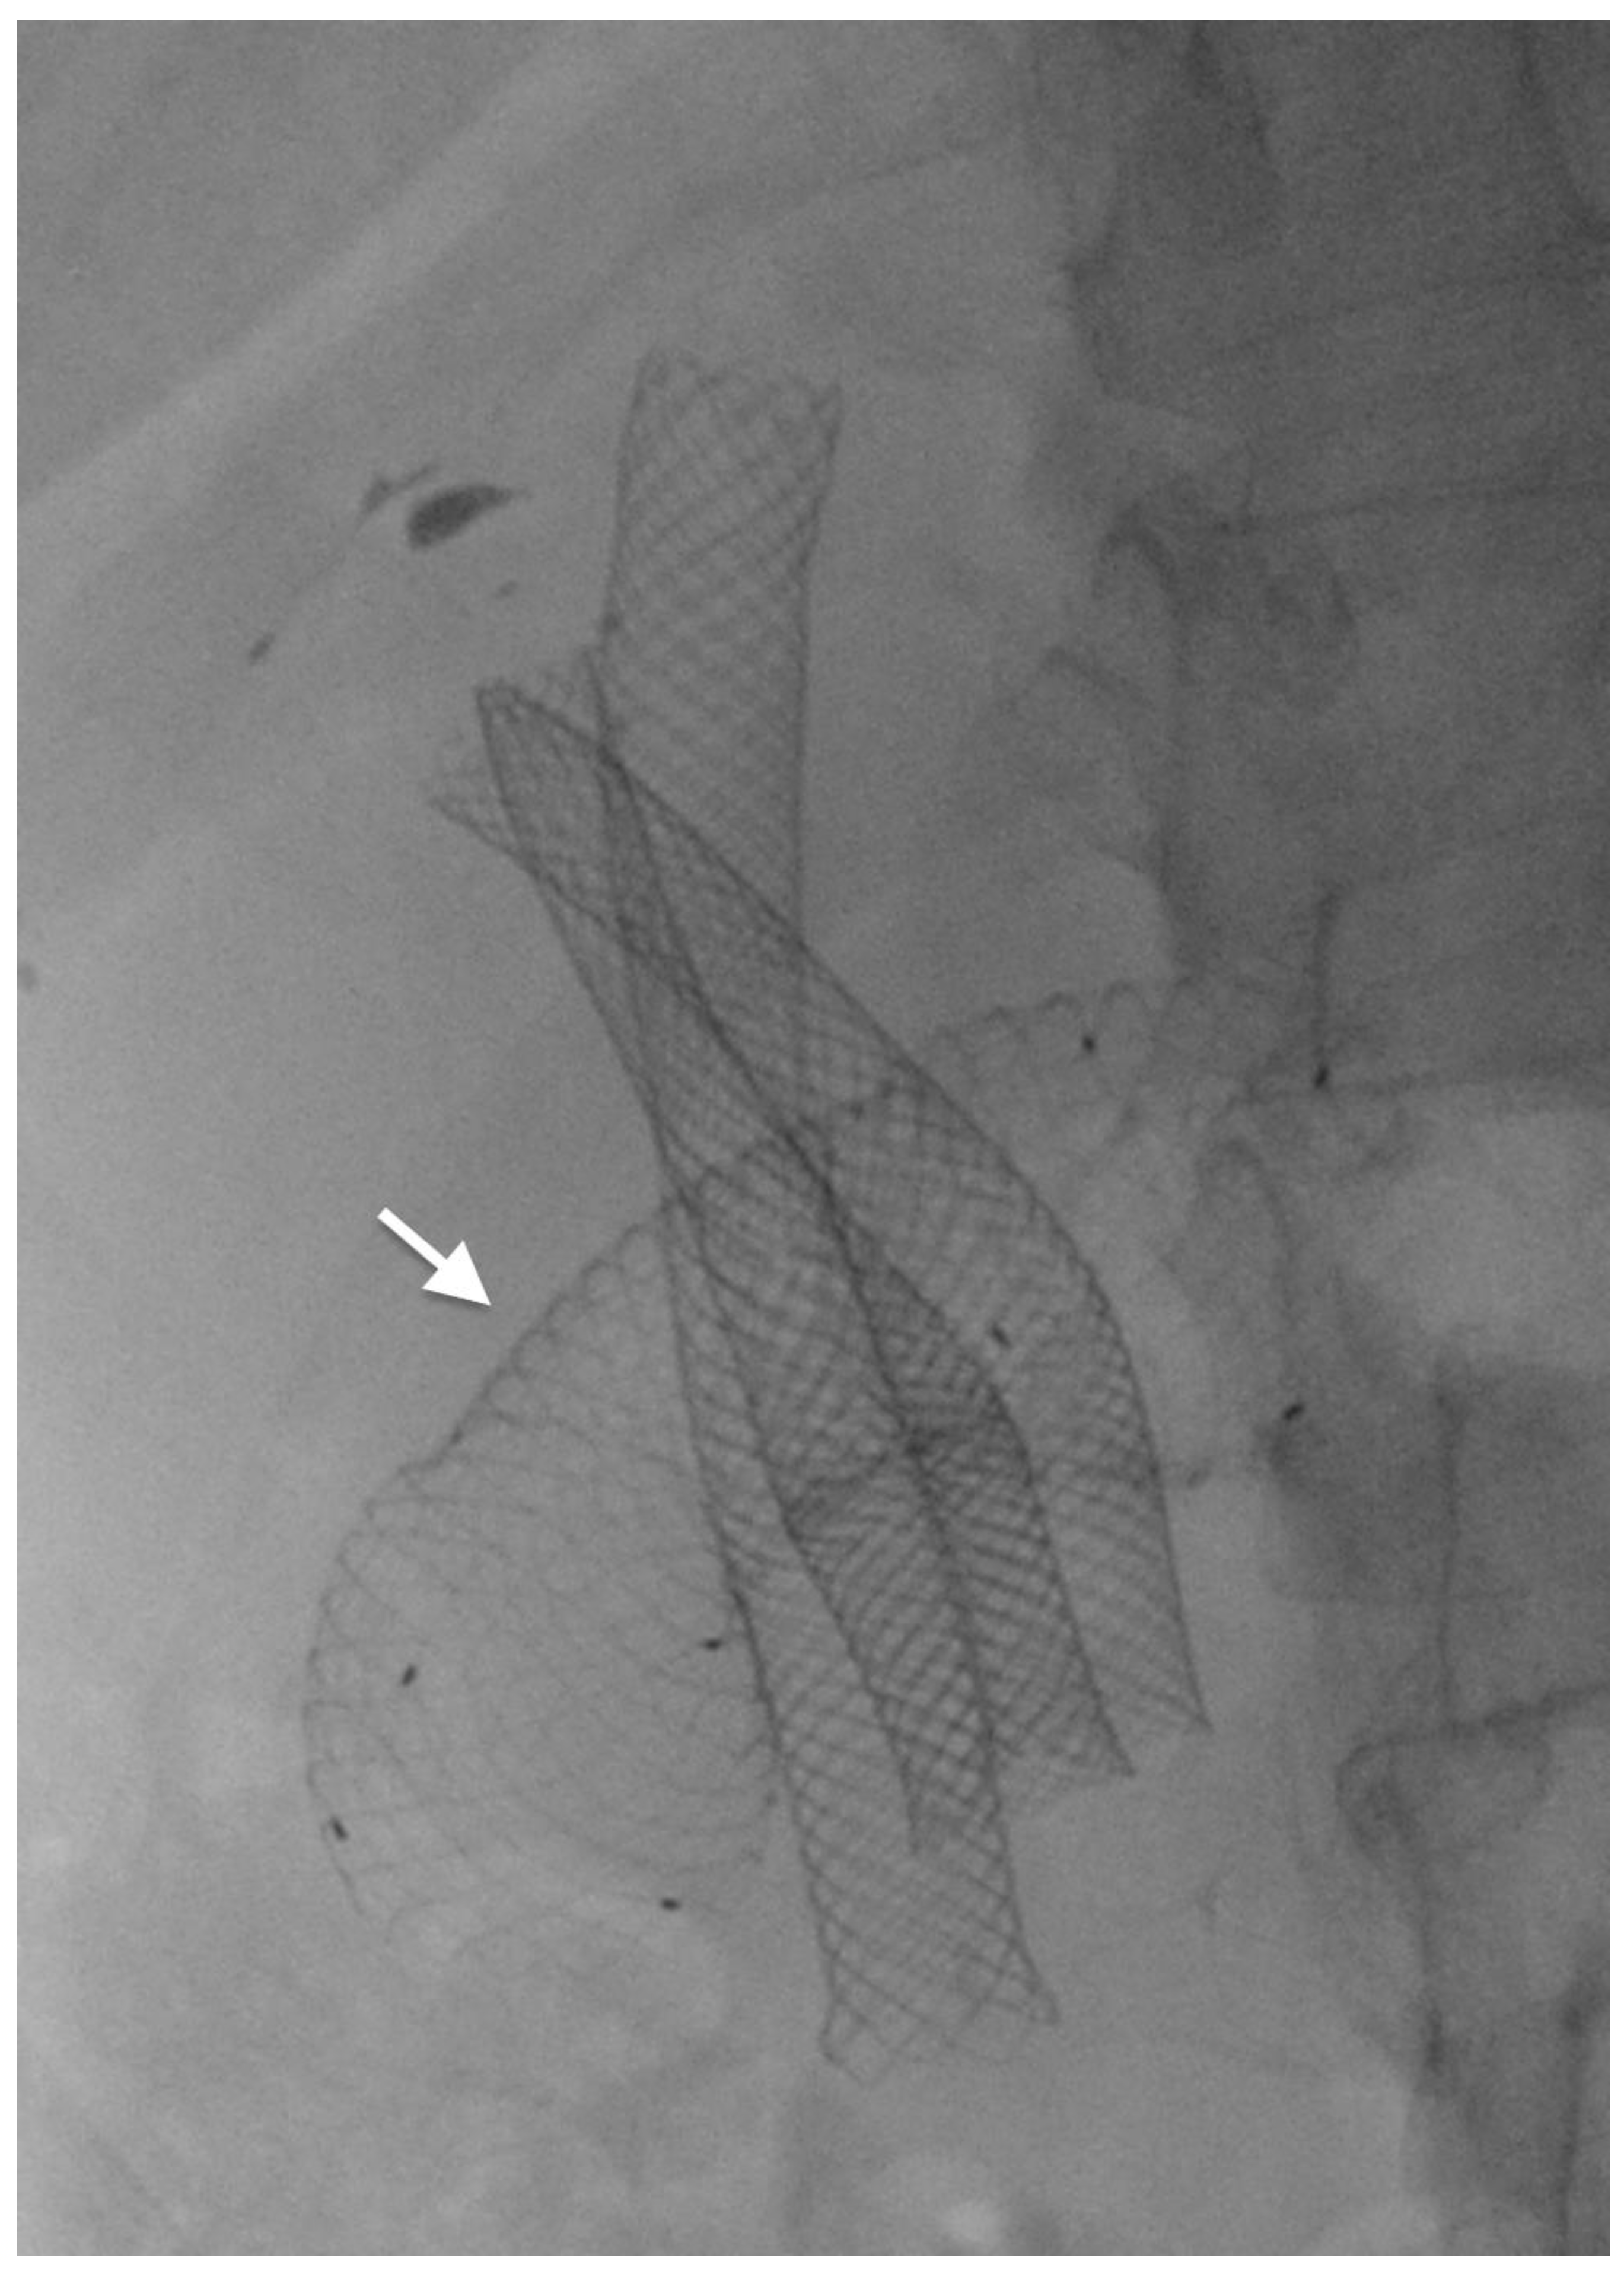

3.1. Endoscopic Self-Expandable Metal Stent

- Yamao, K.; Kitano, M.; Chiba, Y.; Ogura, T.; Eguchi, T.; Moriyama, I.; Yamashita, Y.; Kato, H.; Kayahara, T.; Hoki, N.; et al. Endoscopic placement of covered versus uncovered self-expandable metal stents for palliation of malignant gastric outlet obstruction. Gut 2021, 70, 1244–1252. [Google Scholar] [CrossRef]

- Tringali, A.; Costa, D.; Anderloni, A.; Carrara, S.; Repici, A.; Adler, D.G. Covered versus uncovered metal stents for malignant gastric outlet obstruction: A systematic review and meta-analysis. Gastrointest. Endosc. 2020, 92, 1153–1163.e9. [Google Scholar] [CrossRef] [PubMed]

- Van Halsema, E.E.; Rauws, E.A.J.; Fockens, P.; Van Hooft, J.E. Self-expandable metal stents for malignant gastric outlet obstruction: A pooled analysis of prospective literature. World J. Gastroenterol. 2015, 21, 12468–12481. [Google Scholar] [CrossRef] [PubMed]